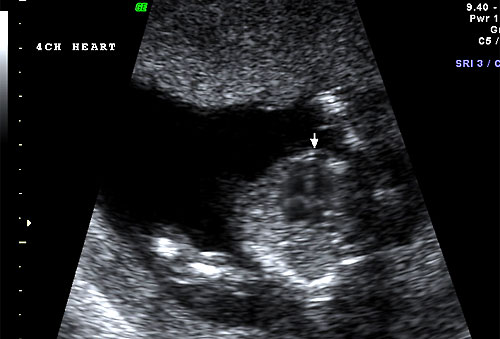

Normal 16 week 4 chamber heart |